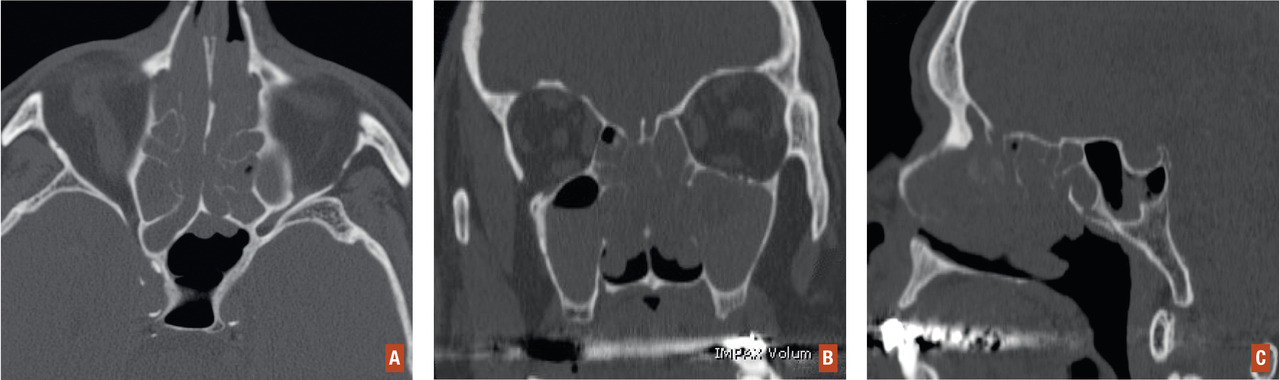

Les clichés standard de la face ne sont d’aucune utilité ; ils ne doivent plus être prescrits en pathologie rhinosinusienne aiguë ou chronique. L’imagerie volumétrique par faisceau conique ou « cone beam »(cone beam computed tomography [CBCT]) est l’examen de référence. L’imagerie par résonance magnétique (IRM) n’a que des indications très limitées et ne doit être prescrite que par le spécialiste ORL. Le cone beam doit être effectué en coupes axiales et coronales, voire sagittales, sans injection de produit de contraste. Il peut être couplé à une tomodensitométrie dentaire si l’on suspecte l’existence de pathologies dentaires apicales. Cet examen doit être fait dans des conditions strictes :

– confirmer le diagnostic topographique (fig. 2 ) ; l’atteinte des cellules ethmoïdales est bilatérale et symétrique ; une atteinte unilatérale doit conduire à suspecter une tumeur et à réaliser une IRM ;

– quantifier l’étendue des lésions ;

– rechercher des lésions associées (lésions apicales dentaires, aspergillose) ;

– analyser les repères anatomiques (risque chirurgical).